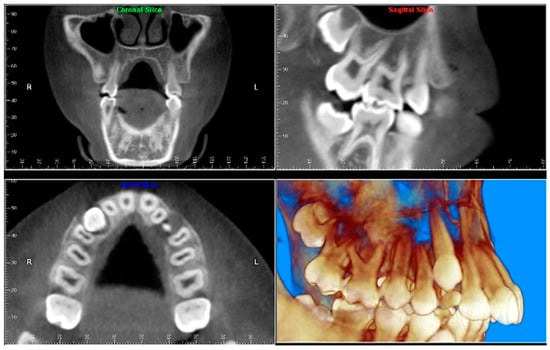

- TMJ and facial asymmetry evaluation. Figure 8, Figure 9 and Figure 10 show a case in which a whole head CBCT was acquired initially due to the presence of facial asymmetry and history of temporomandibular disorders. Figure 8 shows an intraoral photograph with a unilateral posterior crossbite on the right side, a mandibular midline shift to the right side, and an anterior crossbite on the right lateral incisors. Figure 9 shows cross-sectional views of the TMJ, with a very mild flattening of the joints. Figure 10 shows volume rendering of the CBCT volume, demonstrating lack of symmetry of the face, unilateral posterior crossbite observed on the right side involving premolars and molars, and ectopic canines. The benefits of CBCT imaging in this case are the evaluation the TMJ, visualization of the crossbite on the right side via the volume rendering view, and the ability to perform any isometric measurements, if needed.